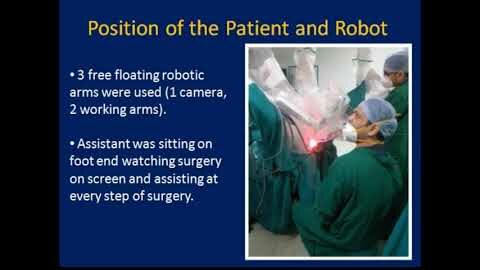

#259- Robotic Surgery in PFUI: Stretching the limits of Robotic technology- Dr. Shrey Jain